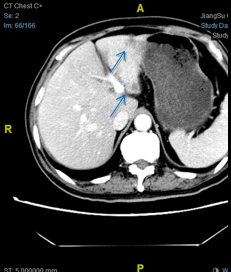

2016-05-12复查CT:左下肺结节缩小,考虑转移;肝脏结节,较前增大,拟转移;上腹术后改变较前相似;右甲状腺病变基本同前。

2016-5-12:

RECIST1.1: 肝脏病灶8.7毫米增大到12.1毫米,左下肺病灶14.5毫米缩小到8毫米。疗效评价:稳定。